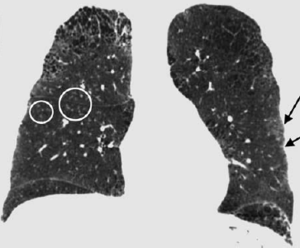

Publication: J Thorac Imaging. 2016 Jan;31(1):29-36. PMID: 26429588| PDF Authors: Zach JA, Williams A, Jou SS, Yagihashi K, Everett D, Hokanson JE, Stinson D, Lynch DA, COPDGene Investigators. Institution: Divisions of Radiology, Biostatistics and Bioinformatics, National Jewish Health, Denver, CO, USA. Background/Purpose: The purposes of this study were to evaluate the effect of smoking status on quantitative computed tomography CT measures of low-attenuation areas (LAAs) on inspiratory and expiratory CT and to provide a method of adjusting for this effect. Materials and Methods: A total of 6762 current and former smokers underwent spirometry and volumetric inspiratory and expiratory CT. Quantitative CT analysis was completed using open-source 3D Slicer software. Funding:

Examples of CN on CT. Coronal CT image of a GOLD 1 subject with moderately extensive visual extent of emphysema. However, the quantitative emphysema score was only 5.1%. The emphysema may have been masked on quantitative assessment by the presence of centrilobular nodules (circled) and patchy ground-glass abnormality (arrows). |